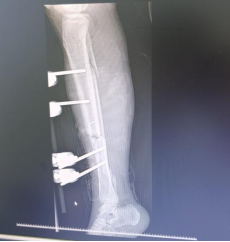

最后一步,就是固定骨骼,重建下肢力線。針對多項粉碎性骨折、骨缺損情況,手術團隊采用外固定支架臨時復位固定,既保證肢體形態,又為二期缺損的骨修復預留空間。

“手術中,患者輸血量高達2400毫升,相當于半個成年人的全身血量。”佛山市康復醫院(佛山市第五人民醫院)骨科住院醫師任庭杰介紹,這是一場艱難的保肢戰,但整個團隊配合極其默契、高效,不到3小時就贏得了手術的成功。